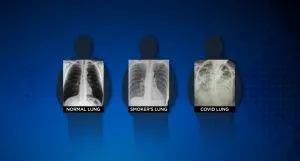

„Ima ljudi koji kažu: 'Dobro sam, nemam nikakvih problema“, a kad im pogledate RTG grudnog koša, imaju jako lošu sliku pluća“, kaže doktorica koja je medijima pokazala tri rendgenska snimka: Jedan snimak zdravih pluća, jedan snimak pluća pušača i jedan snimak pacijenta koji je preležao Covid-19.

RTG snimak zdravog pacijenta pokazuje veliku količinu crnog prostora, što znači da je osoba u stanju da udiše veliku količinu vazduha. S druge strane, RTG pušača pokazuje bijele crte i maglovite mrlje, što ukazuje na upalu i oštećenje zidova pluća. Rendgen pluća osobe koja je preležala Covid-19 potpuno je bijel, kao da se nad njih nadvio bijeli oblak.

Takve promjene obično ukazuju na to da su pluća puna tečnosti, kao i bakterija. To takođe znači da pacijent nije u mogućnosti da unosi dovoljnu količinu kiseonika, što bi bilo moguće da su pluća zdrava.

„Pluća ili su prepuna bijelih gustih mrlja, ili se cijela pluća pretvore u bijeli oblak. Ako sad i ne osjećate probleme, RTG snimak pokazuje da biste ih vremenom mogli imati“, kaže doktorica za CBS DFW. Neki su pacijenti, dodaje, završili sa trajnim oštećenjima pluća ili ožiljcima, ali nije jasno da li to važi za sve pacijente.